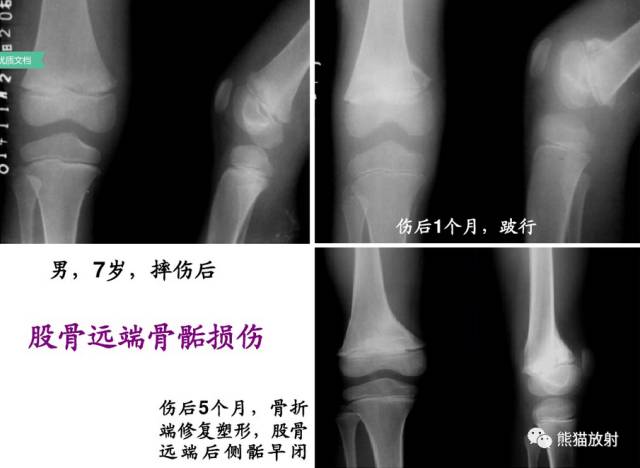

(上图)骨骺轻微向背侧、内侧移位,1-2周后随访骺板处可见成骨反应。

第一型(Ⅰ型) 骨骺分离,分离一般发生在生长板的肥大层,故软骨的生长带留在骨骺一侧,所以多不引起生长障碍;婴幼儿骺板软骨层较宽,容易发生骨骺分离,据统计,占骨骺损伤的15.9%;唯一的x线征象是骨化中心移位,该型复位容易,预后良好;而股骨头骨骺分离由于骨骺动脉多被破坏,预后不佳。该型也可见于坏血病、佝偻病、骨髓炎和内分泌疾病所致的病理性损伤。

第五型(V型) 骺板挤压性损伤,少见,占骨骺损伤的1%。由于严重暴力损伤造成,相当于骺板软骨的压缩骨折,有学者指出此型损伤只发生在一个方向活动的关节,如膝关节和踝关节。由于软骨细胞严重损伤破坏或来自骨骺营养血管广泛损伤,导致骺板早闭和生长停止。逐渐出现骨骼变形和关节畸形 ,但早期X线表现常常为阴性结果,多在晚期发生生长障碍时才能作出诊断。